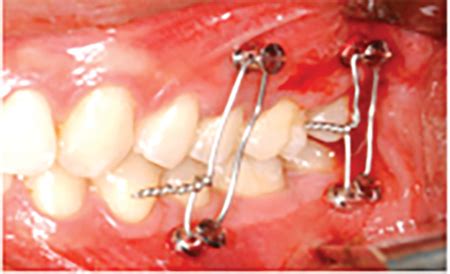

Disadvantages Of Jaw Wiring Maxillofacial Hardware Surgery T